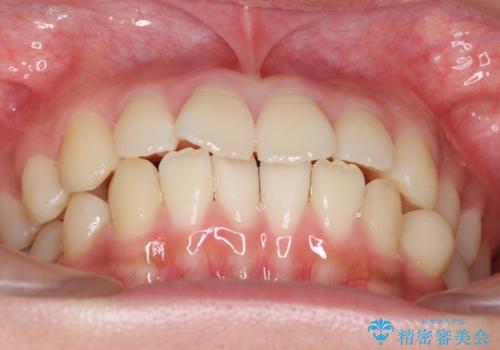

- 前歯のがたつきを気にして来院。

左下の小臼歯が捻転し、反対咬合になっていました。

先にワイヤーで部分矯正を行ってから、インビザラインの部分矯正を行いました。

先に難しい部分をワイヤー矯正することで、インビザラインの部分矯正コースで短期間で予算も抑えて確実に治すことができます。

専門的な話になりますが、下顎の小臼歯は円柱状の形をしており、インビザライン単独では捻転はほぼ治りません。

今回は左下の小臼歯が捻転が強く、そこが反対咬合になっていたため事前に部分矯正を行いました。